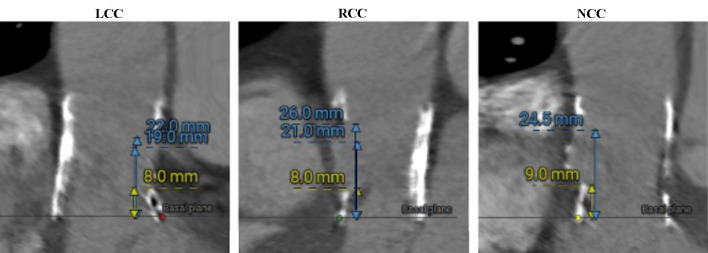

The natural progression of bioprosthetic valve degeneration over time requires further interventions for those experiencing symptomatic prosthesis dysfunction. Transcatheter aortic valve replacement (TAVR) emerges as a promising therapeutic option to alleviate symptoms in such patients. The valve-in-valve (ViV) technique eliminates the necessity for repetitive open-heart surgical procedures, offering particular advantages for individuals with higher surgical risks. In this report, we describe the case of a 78-year-old female patient presenting with severe symptomatic aortic restenosis of a biological aortic valve implanted 5 years prior. Given the patient's high surgical risk, a transcatheter ViV implantation was chosen as the treatment approach. Utilizing a balloon-expandable valve, the intervention resulted in the successful implantation of a functional TAVR, resulting in symptom relief and enabling a fast discharge from the hospital.